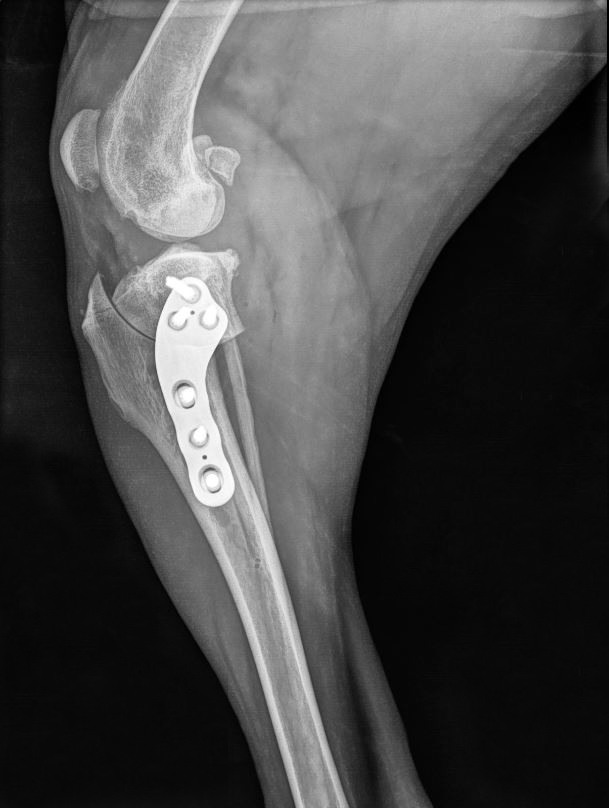

Die Tibial Plateau Leveling Osteotomy (TPLO - Operation) ist ein chirurgisches Verfahren, das häufig zur Behandlung von Kreuzbandrissen (CCL) bei Kleintieren, insbesondere Hunden, eingesetzt wird. Das kraniale Kreuzband entspricht dem vorderen Kreuzband (ACL) beim Menschen und spielt eine entscheidende Rolle bei der Stabilisierung des Kniegelenks.

Ein Riss des kranialen Kreuzbands führt zu Instabilität im Kniegelenk, was Schmerzen, Lahmheit und unbehandelt schließlich Arthrose verursacht. Die TPLO behebt diese Instabilität, indem sie die Biomechanik des Kniegelenks verändert, anstatt das Band selbst zu ersetzen.

Die LeiLOX TPLO-Platten wurden mit höchster Sorgfalt für die anatomische Integrität entwickelt und sind so geformt, dass sie sich optimal an die natürliche Kontur des Knochens anpassen. Diese anatomische Passform erleichtert die präzise Positionierung, steigert die chirurgische Effizienz und minimiert gleichzeitig vaskuläre Schäden am fixierten Knochenabschnitt. Die Plattenunterseite ist nur in minimalem Kontakt zum Knochen. Dadurch wird die Heilung beschleunigt und das Risiko postoperativer Komplikationen reduziert.

Wir stellen die neueste Ergänzung des LeiLOX TPLO-Systems vor: die TPLO Swing Titan-Option. Neben einer überlegenen Biokompatibilität im Vergleich zu traditionellen Edelstahlimplantaten zeichnen sich die TPLO Swing Titan-Implantate durch ein gewölbtes Design aus, das von den natürlichen Konturen der Tibia inspiriert wurde. Benannt nach ihrer markanten „Schwingen“-Form, fügen sich die TPLO Swing-Implantate nahtlos in den Knochen ein, verbessern die Stabilität und fördern eine optimale Heilung. Durch ihre hervorragende Biokompatibilität verringern die Implantate zusätzlich die Wahrscheinlichkeit von negativen Reaktionen und sorgen für eine problemlose Integration in das umgebende Gewebe.